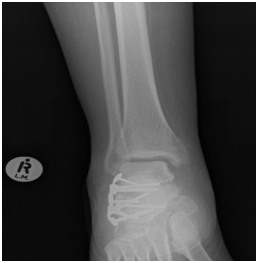

Radiological assessment shows

L3 unstable spine fracture, Right intara-articular calcaneal fracture of joint depression type, Saunder’s III AC3,4(Figure 1 & 2).

Figure 1 CT Calcaneus showing multi fragmentery intra articular fracture.

Figure 2 CT Calcaneus showing joint depression and intra articular extension.